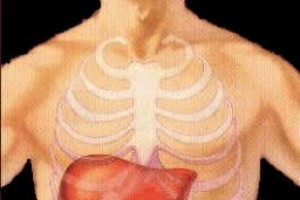

Pesquisadores desenvolvem artificialmente órgã...

"Para cada nova doença que surge, milhares de pesquisas são nec...